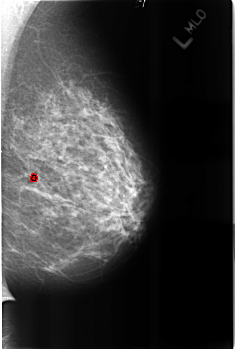

B_3222_1.LEFT_MLO

LEFT_MLO LINES 4528 PIXELS_PER_LINE 3048 BITS_PER_PIXEL 12 RESOLUTION 50 OVERLAY

FILE: B_3222_1.LEFT_MLO.OVERLAY

TOTAL_ABNORMALITIES 1

ABNORMALITY 1

LESION_TYPE CALCIFICATION TYPE LUCENT_CENTER DISTRIBUTION N/A

ASSESSMENT 2

SUBTLETY 3

PATHOLOGY BENIGN_WITHOUT_CALLBACK